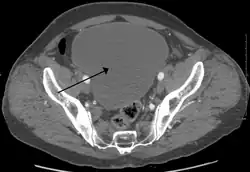

Urinary retention with greatly enlarged bladder as seen by CT scan.

As seen on axial CT